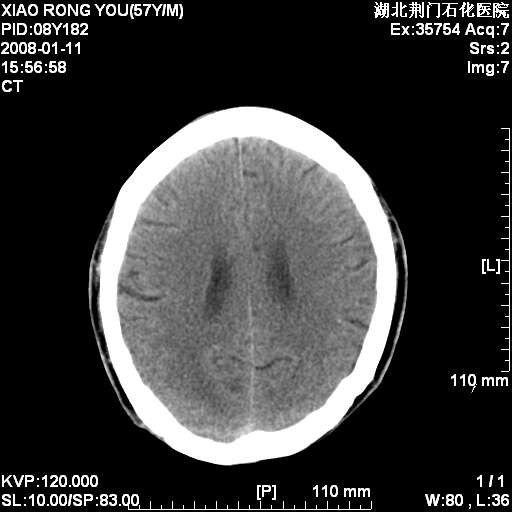

男性,68岁,多年肺结核病史。最近ct复查右肺有占位。

头部平扫